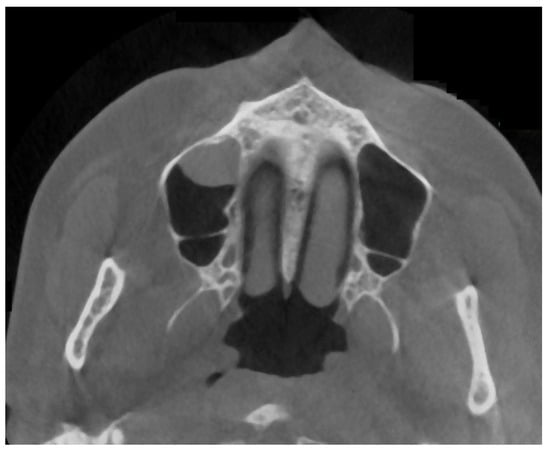

2.2. Cone Beam Computed Tomography Characteristics

2.3. Methods—Classification Proposal